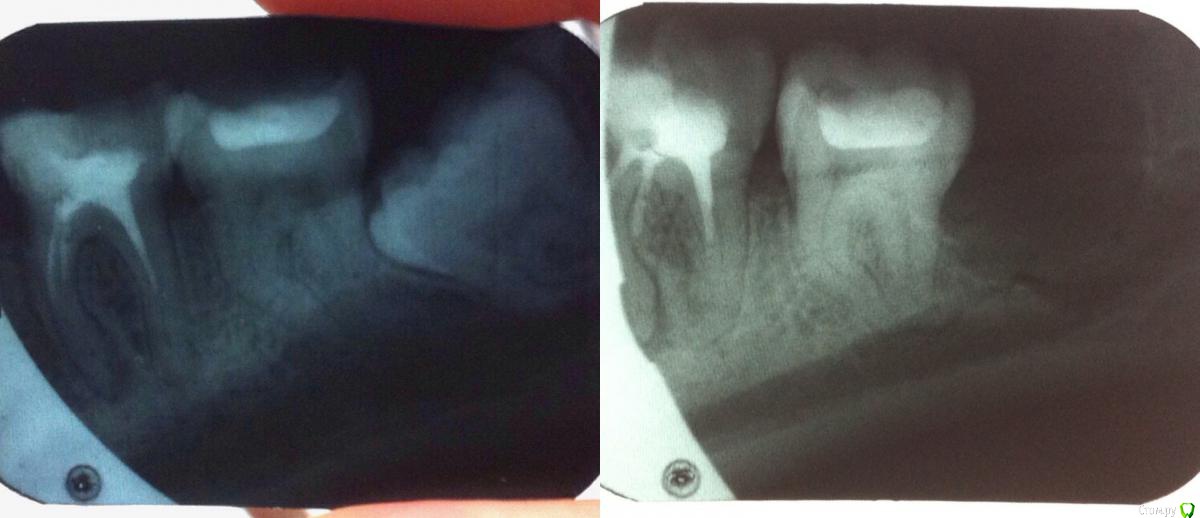

Ellie_58 Опубликовано 22 февраля, 2018 Поделиться Опубликовано 22 февраля, 2018 У меня был снимок после удаления 48 зуба, на котором увидели воспаление (кисту) 46 и сказали лечить (так он меня не беспокоил). В одной больнице два врача пытались пройти каналы, но не смогли. Первый сказал боится оставить инструмент, второй - все из-за предыдущего лечения-пломбировки (не особо понятная для меня причина). Третий врач в другой больнице выдала новый вариант, что каналы не доходят до конца корня, а разветвляются. Но всё-таки она попробовала и прошла один канал (судя по апекслокатору) и сказала, что лекарство кальций через него пройдет к кисте. Еще она сказала, что у меня есть небольшой обломок инструмента, но это нестрашно. В итоге она прекратила попытки пройти каналы с той же фразой, что не хочет оставлять инструменты в зубе. Снимок у меня только после попыток первого врача, но надеюсь на нем видно реально ли каналы разветвляются и их нельзя пройти? Поможет ли такое лечение? В каком случае удалять зуб? И после попыток зуб по разному то болит, то проходит - что это значит? Ссылка на комментарий